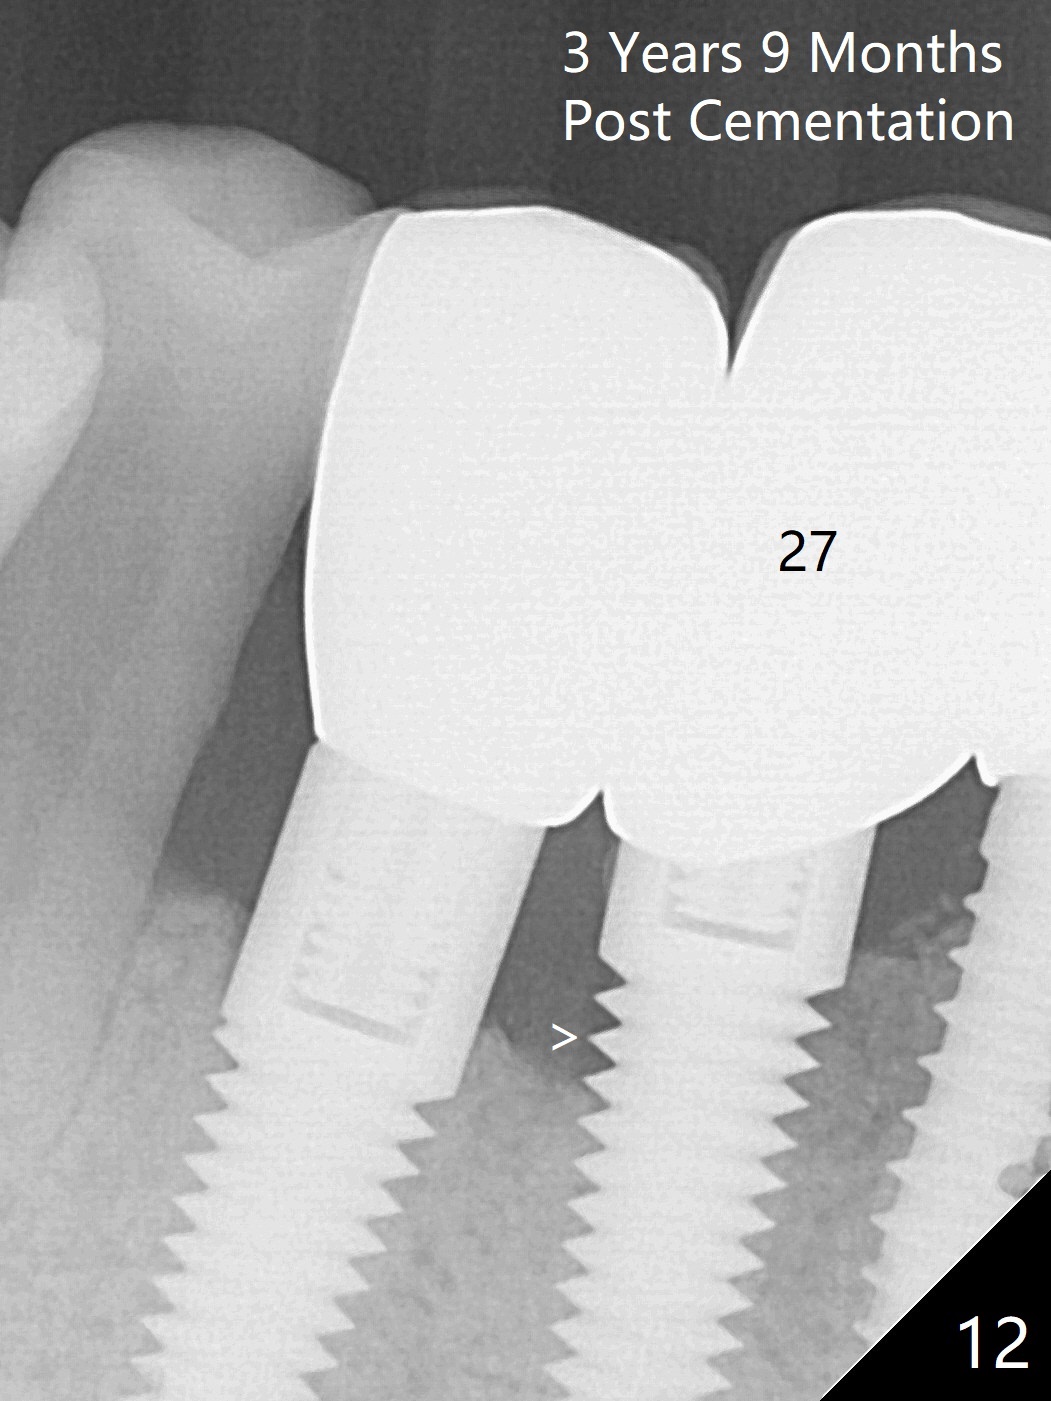

The implants remain asymptomatic years months post cementation (Fig.12), while the one at #27 is associated with buccal and lingual swelling and hemorrhage and bone loss (Fig.13). There is bone loss distal to #27 without symptom 3 years 9 months post cementation (Fig.12). Periimplantitis develops buccal and lingual 4 years 5 months post cementation (coronavirus, Fig.13). Sticky bone and PRF are used after debridement. There is no discomfort 7 days postop (Fig.14,15).